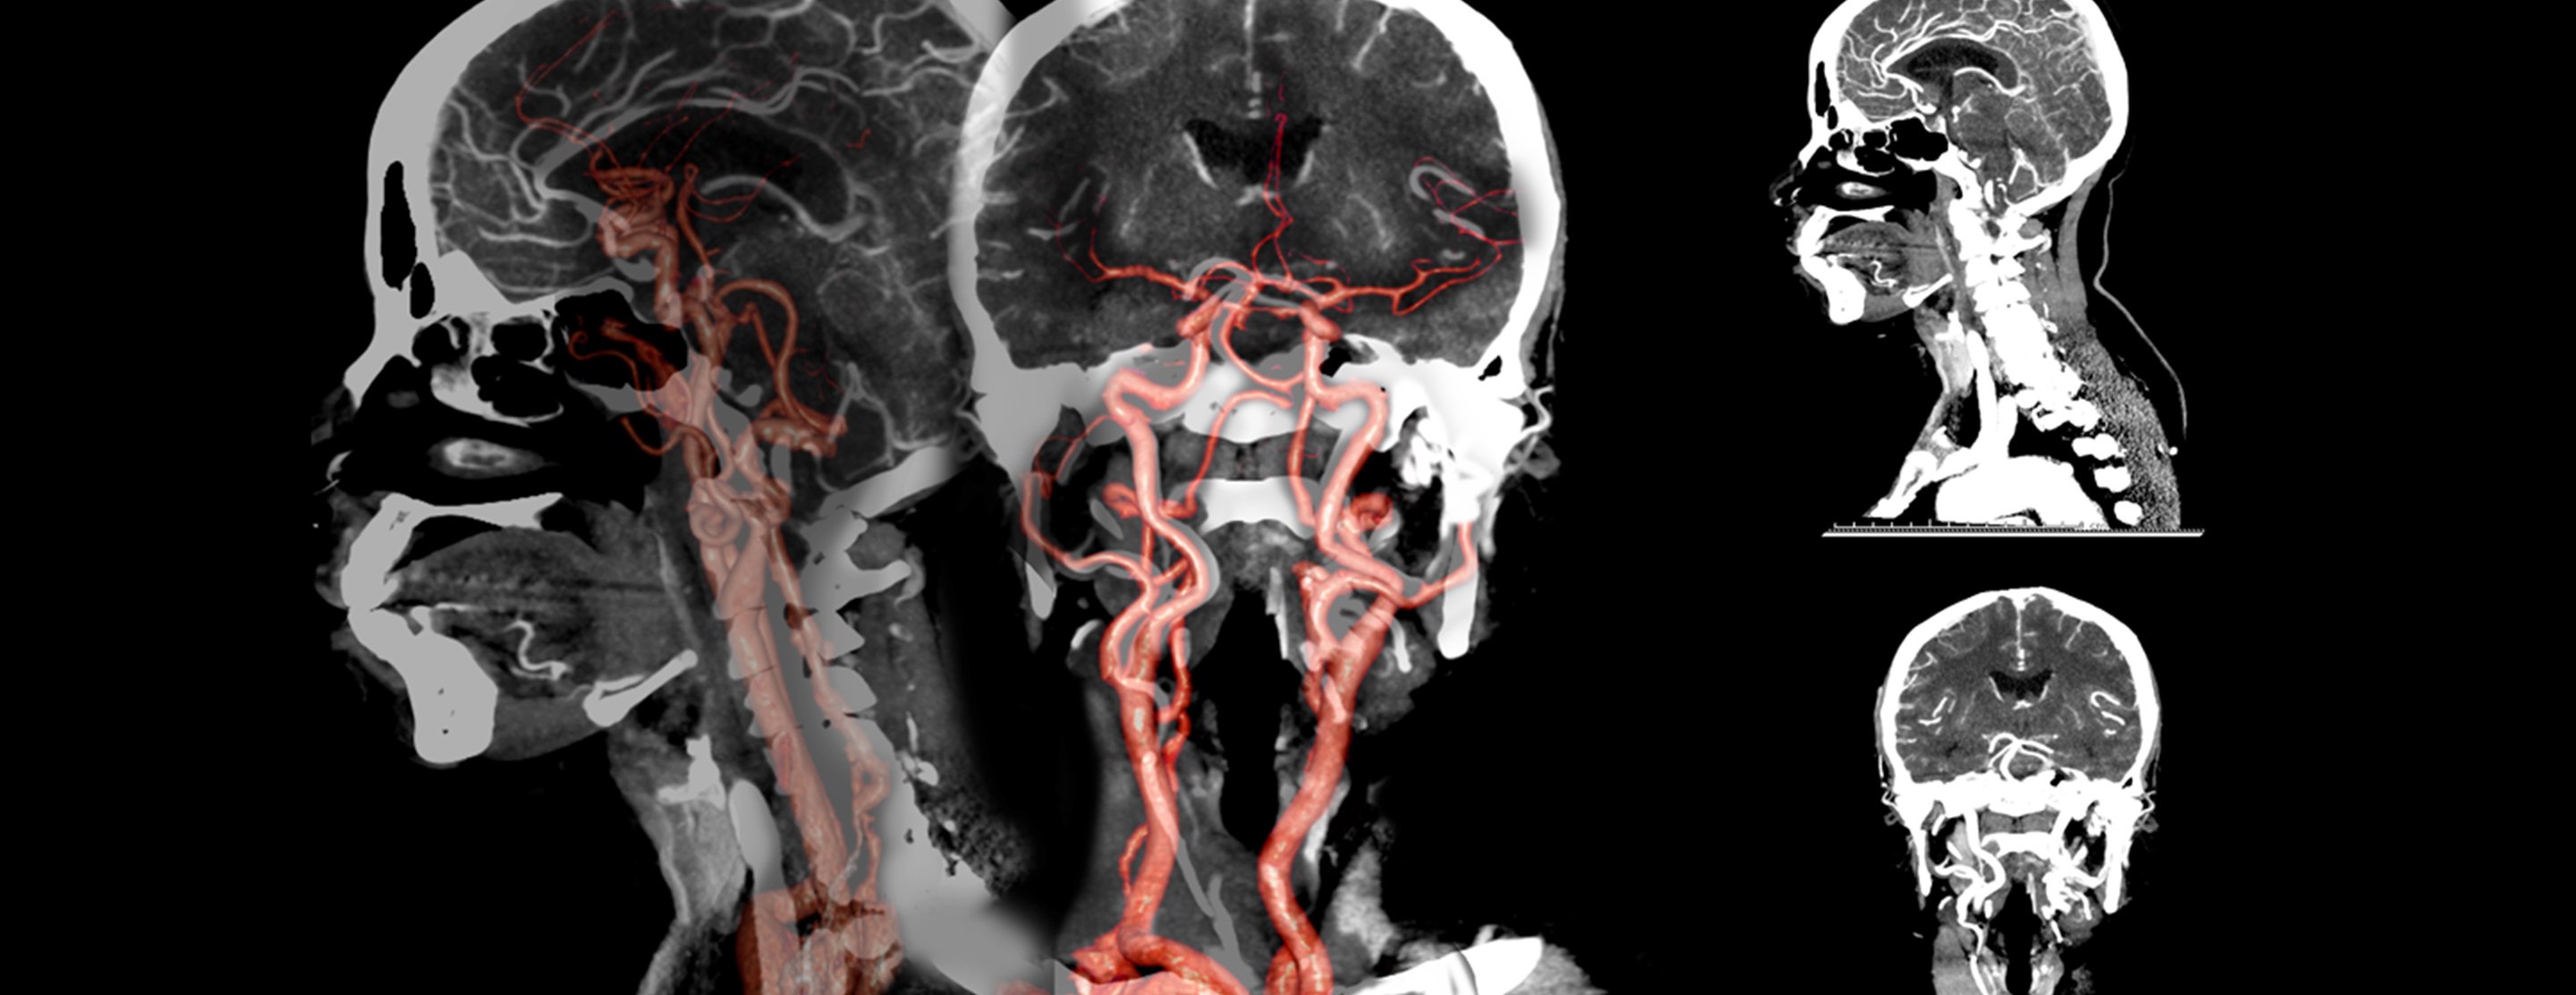

CT angiography - head and neck

CT angiography (CTA) combines a CT scan with the injection of dye. CT stands for computed tomography. This technique is able to create pictures of the blood vessels in the head and neck.

A computer creates many separate images of the body area, called slices. These images can be stored, viewed on a monitor, or printed on film. Three-dimensional models of the head and neck area can be created by stacking the slices together.